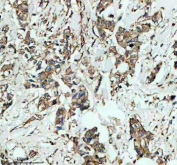

Immunohistochemical staining of GSTK1 using anti-GSTK1 antibody. GSTK1 was detected in a paraffin-embedded section of human breast cancer tissue. Heat mediated antigen retrieval was performed in EDTA buffer (pH 8.0, epitope retrieval solution). The tissue section was blocked with 10% goat serum. The tissue section was then incubated with 2 ug/ml rabbit anti-GSTK1 antibody overnight at 4oC. Peroxidase Conjugated Goat Anti-rabbit IgG was used as secondary antibody and incubated for 30 minutes at 37oC. The tissue section was developed using an HRP secondary and DAB substrate.